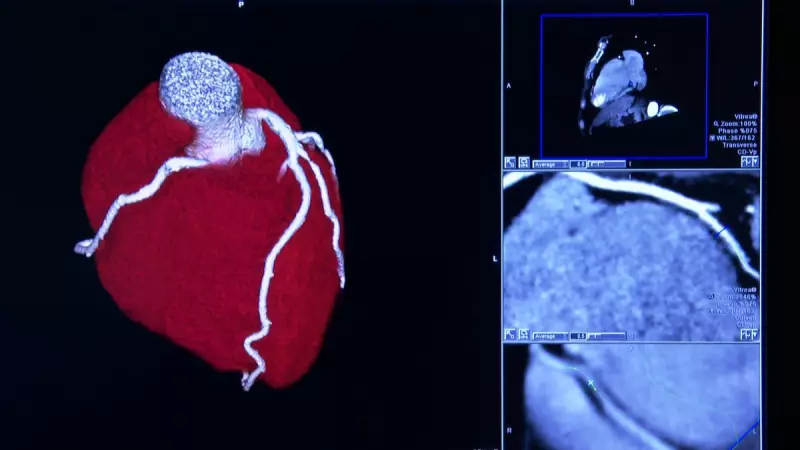

O equipamento revolucionário combina duas técnicas avançadas de imagem médica: a espectroscopia infravermelha e o ultrassom intravascular. A espectroscopia infravermelha é uma ciência que analisa as interações entre radiação e matéria, enquanto o ultrassom intravascular fornece imagens detalhadas do interior das artérias. Juntas, essas tecnologias permitem detectar e analisar placas de gordura nas artérias com precisão inédita.

O cardiologista intervencionista Hideo Kajita, entrevistado pelo Hora News, explica o funcionamento do método: "É um cateter que colocamos como exame complementar. Ele emite uma luz infravermelha para fazer uma análise da composição da placa de gordura desse paciente. Em algumas situações, essa placa de gordura pode ser uma placa mais vulnerável e consequentemente tem uma maior tendência de ruptura, o que levaria o paciente a desenvolver um infarto agudo do miocárdio".